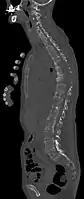

- Vues de fractures pathologiques

Fracture pathologique du bras gauche sur une métastase osseuse de cancer du sein

Scintigraphie corps entier avec 99mTc-HDP de la patiente avec une fracture du bras due à une métastase du cancer du sein